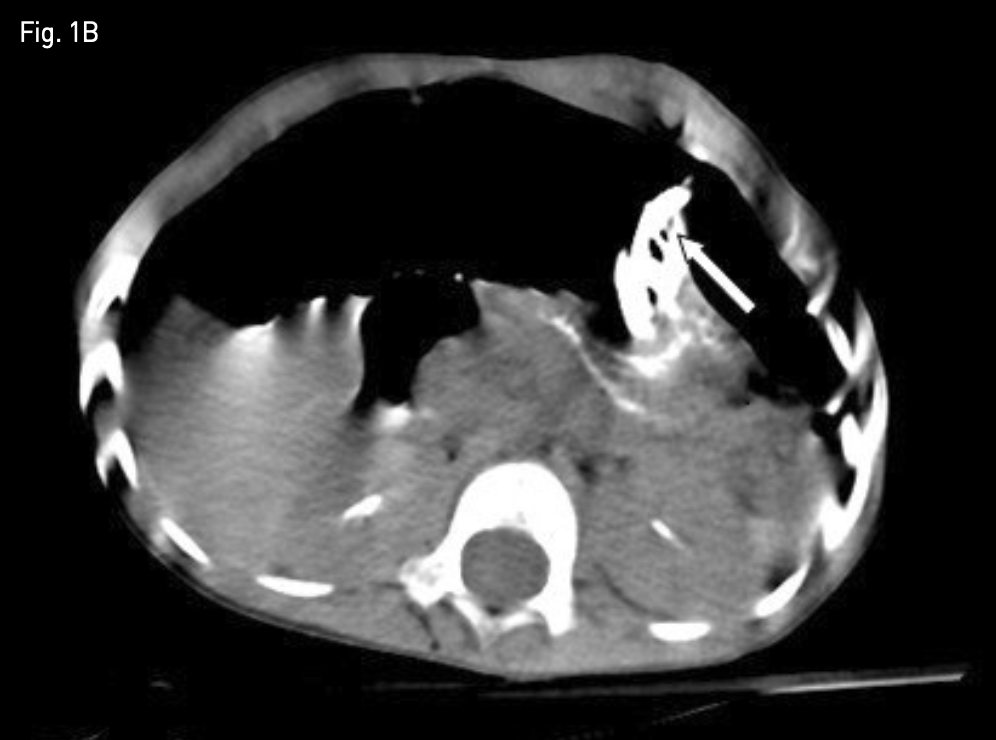

시술 다음 날 추적 관찰 단순 복부 X-ray 촬영에서 기복증이 발생하였고(Fig. 1A), 복부 CT에서는 위 전벽이 전복벽에 완전히 밀착되지 않았음을 확인하였다 (Fig. 1B). 기복증의 양이 작아 추적 관찰을 하였으나, 갈수록 양이 많아지고, 아울러 환아의 전신 상태가 나빠지기 시작하였음.

Fig. 1B

Non-contrast axial abdominal CT image, obtained 1 day after percutaneous radiologic gastrostomy shows significant gap between anterior abdominal wall and anterior wall of the stomach with first T-fastener (white arrow).